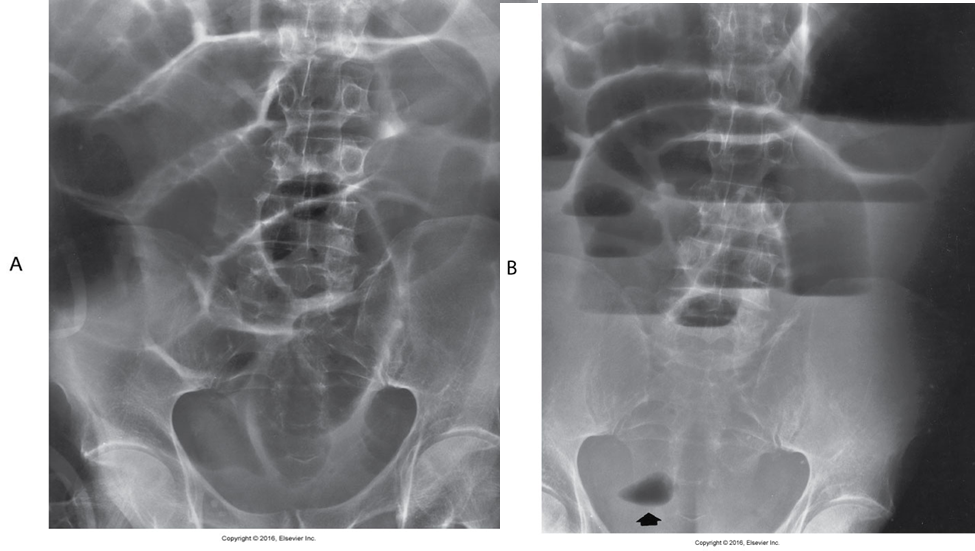

Volvulus

refers to a twisting of the bowel on itself.

May cause obstruction.

Most common sites:

Cecum

Sigmoid

Water soluble enema may be therapeutic and resolve obstruction.

Sigmoid Volvulus

Radiological Appearance:

Coffee bean sign

Caecal volvulus

Radiological Appearance:

Kidney bean sign